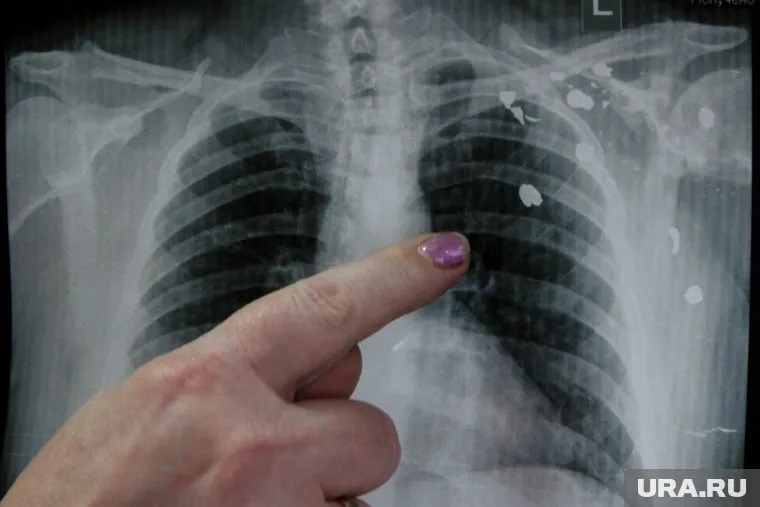

Среди российских подростков может начаться эпидемия EVALI (повреждение легких, связанное с вейпингом — прим. URA.RU), которая бушует в США среди любителей вейпов и электронных сигарет. Таким мнением с URA.RU поделилась руководитель Центра профилактики и контроля потребления табака НМИЦ терапии и профилактической медицины Минздрава России Маринэ Гамбарян.

«Электронные сигареты вызывают никотиновую зависимость. Вещества, входящие в состав аэрозолей электронных сигарет, в частности вкусовые добавки и ароматизаторы, оказывают пагубное воздействие на ткани бронхов и легких и могут стать причиной поражения легких, связанных с вейпингом — EVALI. Это заболевание, распространенное среди молодых людей в США. Появление EVALI — результат эпидемии потребления электронных сигарет в Америке. У нас пока нет эпидемии, но она не за горами, если не регулировать распространение и потребление электронных сигарет и не принимать меры», — сказала Маринэ Гамбарян.